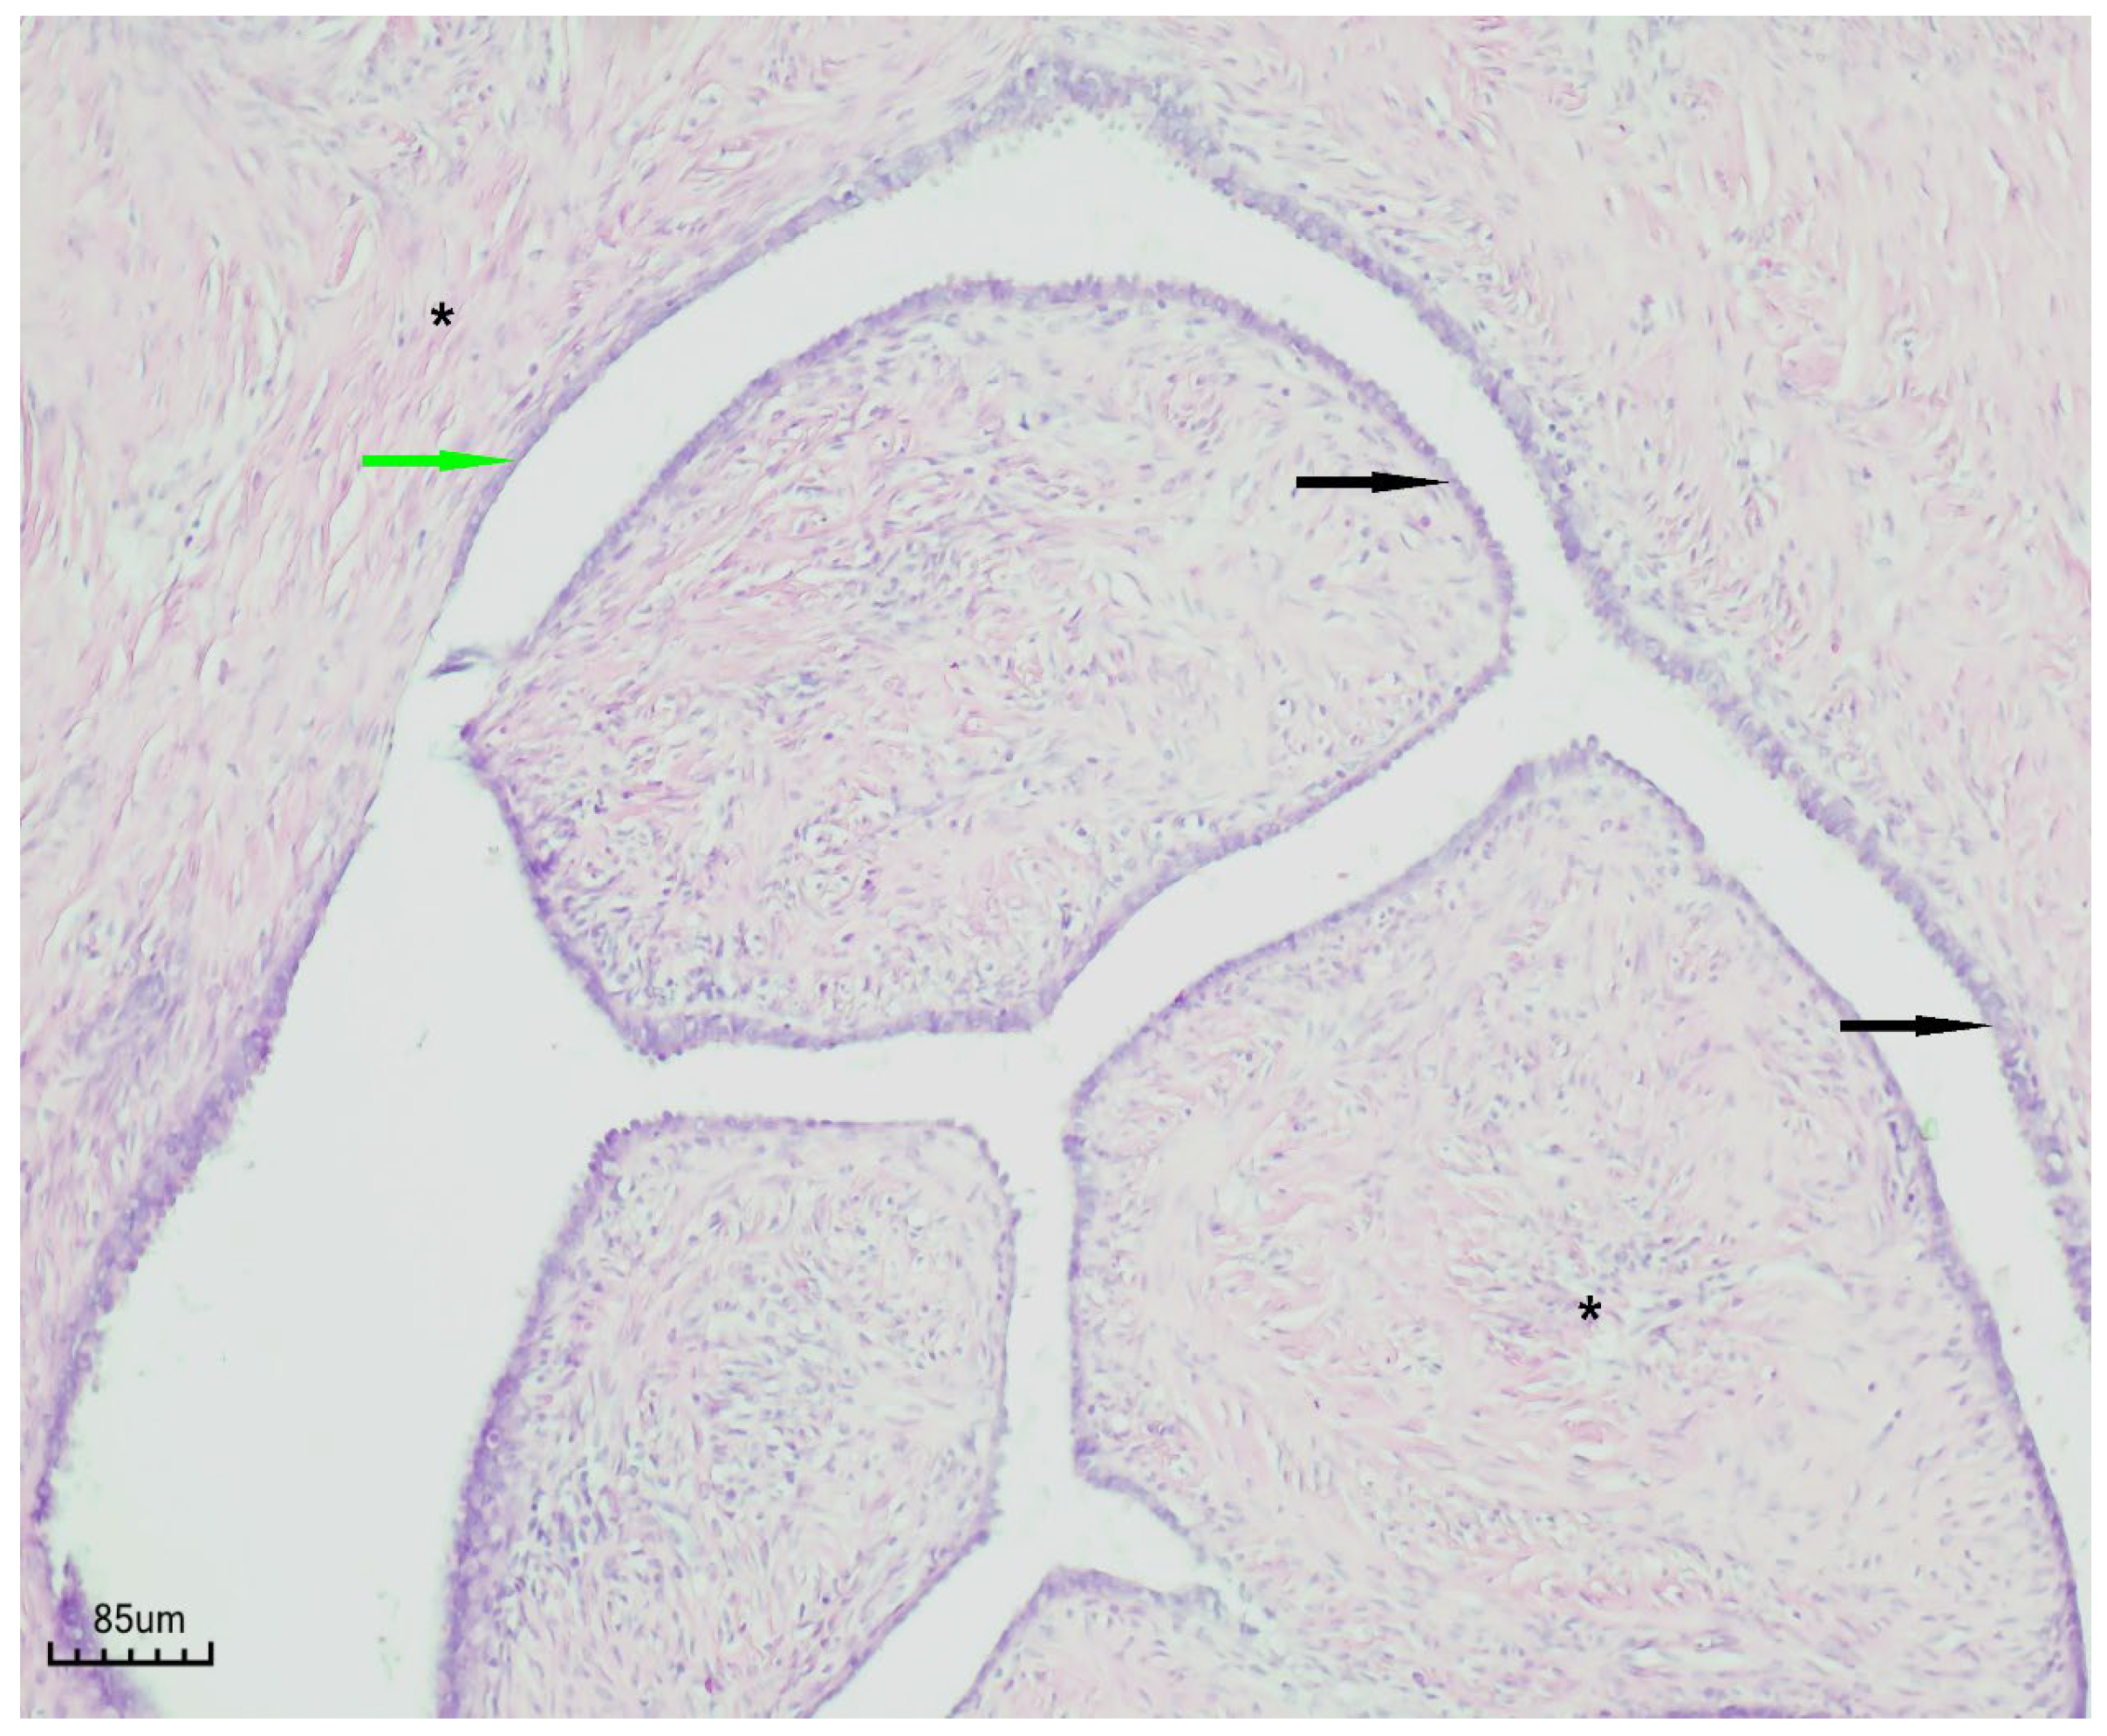

3.4. Diagnostic Assessment

The patient was first evaluated using gynecologic ultrasound, including transvaginal sonography (TVS), which is the first-line diagnostic tool for adnexal masses in clinical practice. Transvaginal sonography (TVS) revealed a complex left adnexal mass with cystic morphology, showing well-defined borders and thin internal septations (Figure 1). Subsequently, magnetic resonance imaging (MRI) was performed as a complementary investigation to provide additional characterization of the lesion and to assist in the differential diagnosis with borderline or malignant ovarian tumors.

Figure 1. Transvaginal sonography (TVS) of the left adnexa ( orange arrow) demonstrating a complex ovarian cyst with cystic morphology, thin internal septations, and well-defined borders.